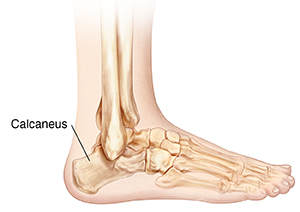

Understanding Calcaneus (Heel) Fracture Repair

The calcaneus is the heel bone. This bone may become fractured during a high-energy injury. This includes such things as a fall from a height, a twisting injury to the ankle, or a car accident. The heel may break in several places. The fracture may cause your foot to become misshapen. It may be difficult or impossible to walk on. The injury is often very painful.

A fracture of the heel bone may result in multiple pieces of broken bone. The broken pieces may be displaced. This means they no longer line up correctly with each other. You may need surgery to repair a heel fracture so you can use your foot again. During surgery, the surgeon moves the pieces of bone back into place. The surgeon then puts in metal devices (internal fixation) to hold the bone pieces in place while they heal.